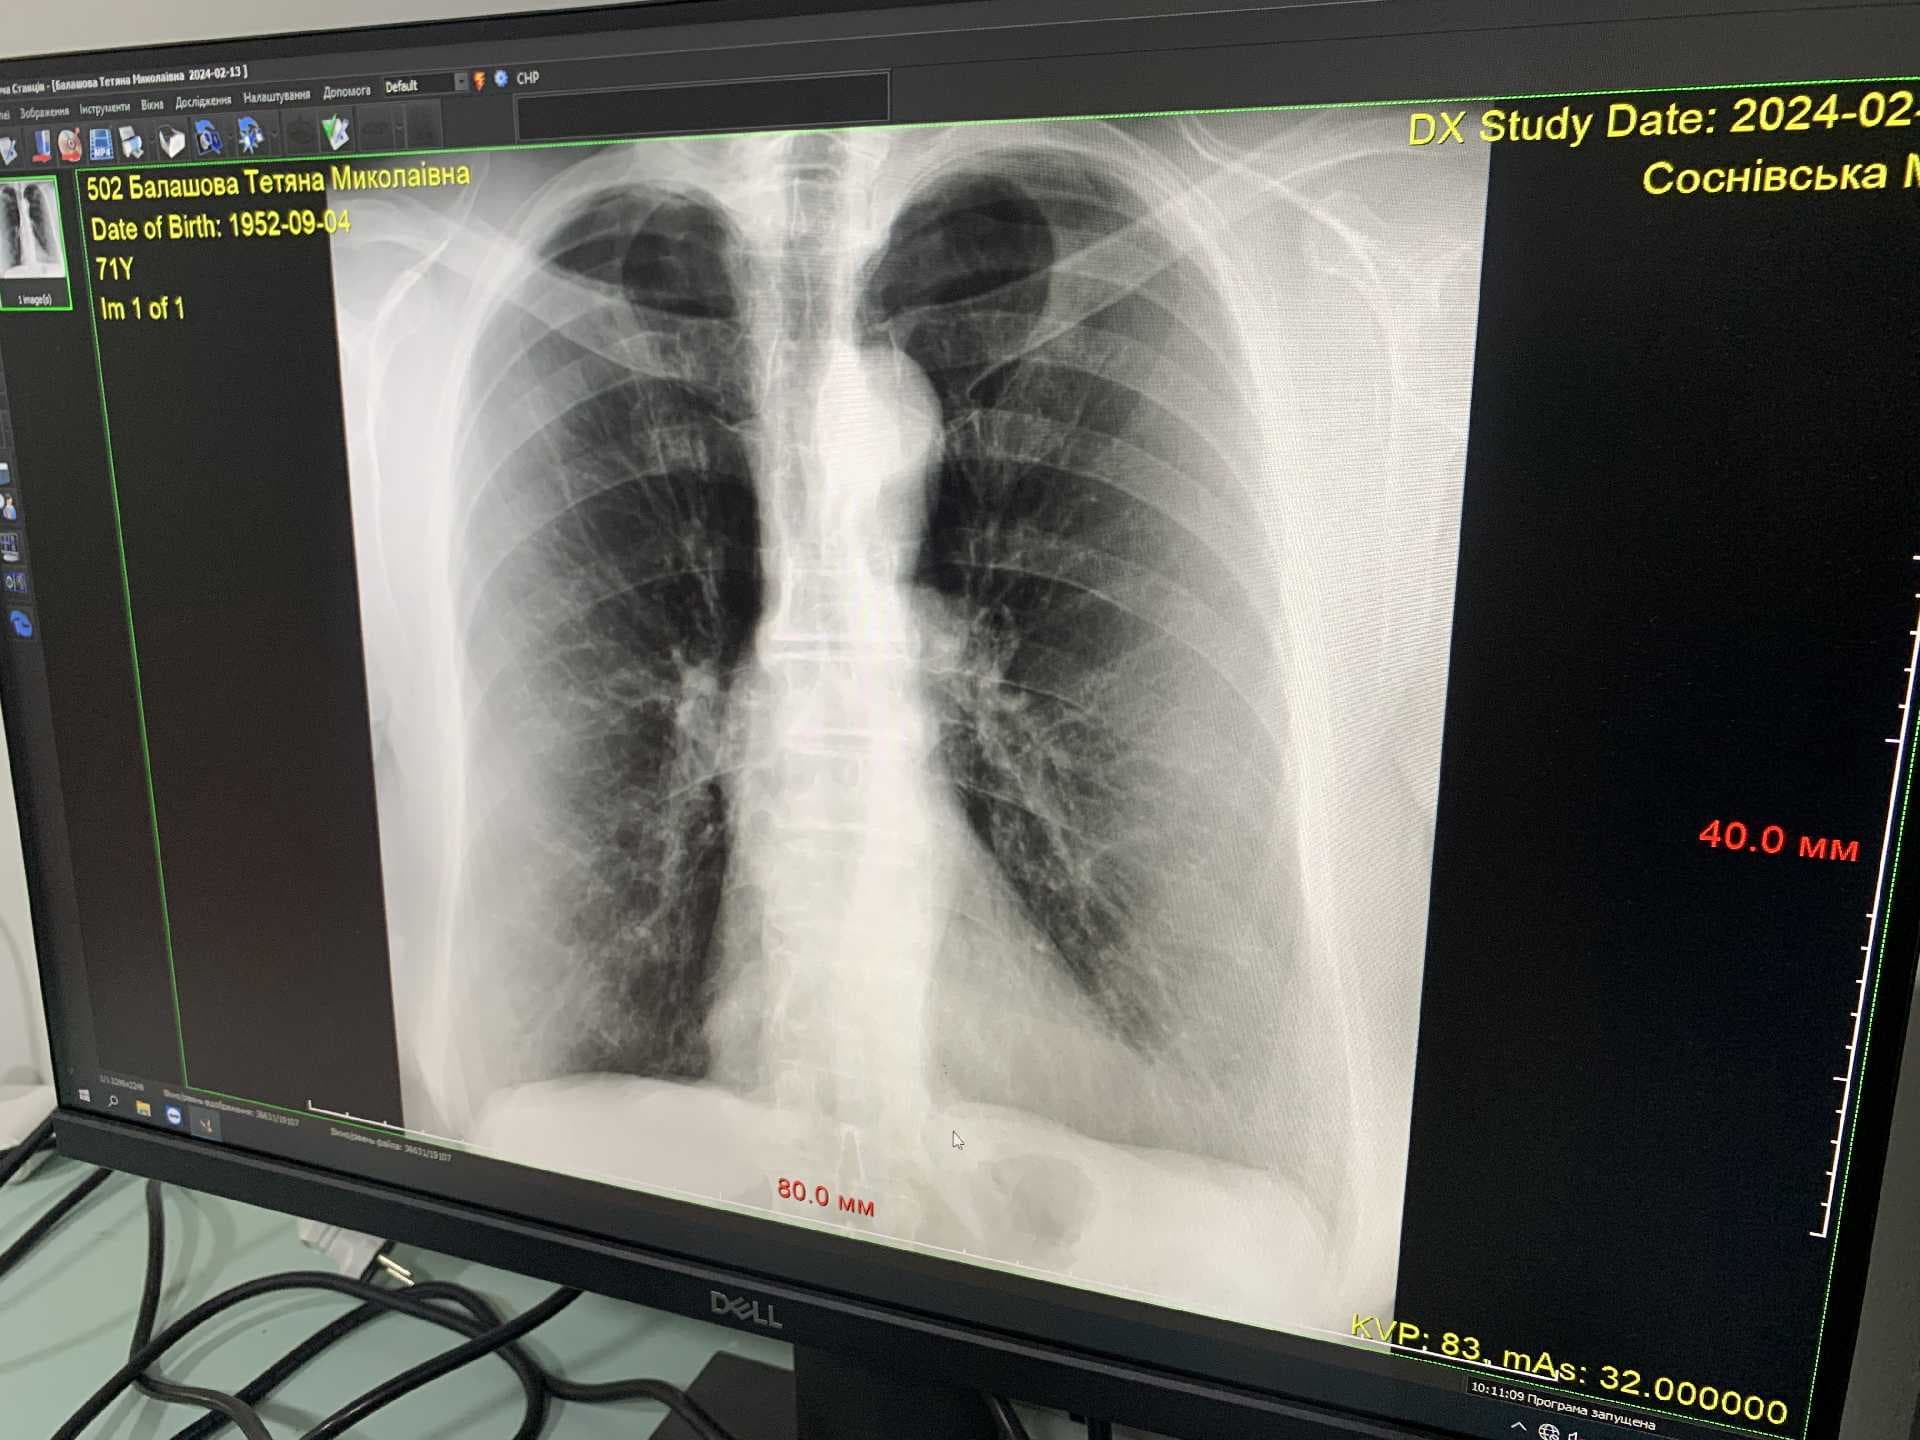

У рентген-кабінеті працює кваліфікований лікар-рентгенолог, молодша медсестра та два лаборанти, які допомагають лікарю в підготовці пацієнтів та обробці зображень. За словами медиків, найбільше людей, що звертаються до них, мають травми кісток, хребта, суглобів, пазух носа та легенів. Для того, аби скористатися послугами рентгену, пацієнтам потрібно мати скерування від сімейного лікаря або іншого спеціаліста.

«Функціонування такого рентген-кабінету є важливим кроком у покращенні якості медичної допомоги населенню міста та району. Завдяки новому обладнанню та кваліфікованому персоналу, пацієнти можуть отримати швидку та точну діагностику свого стану здоров\'я та призначення оптимального лікування» - зауважив директор Соснівської міської лікарні Юрій Кінах.